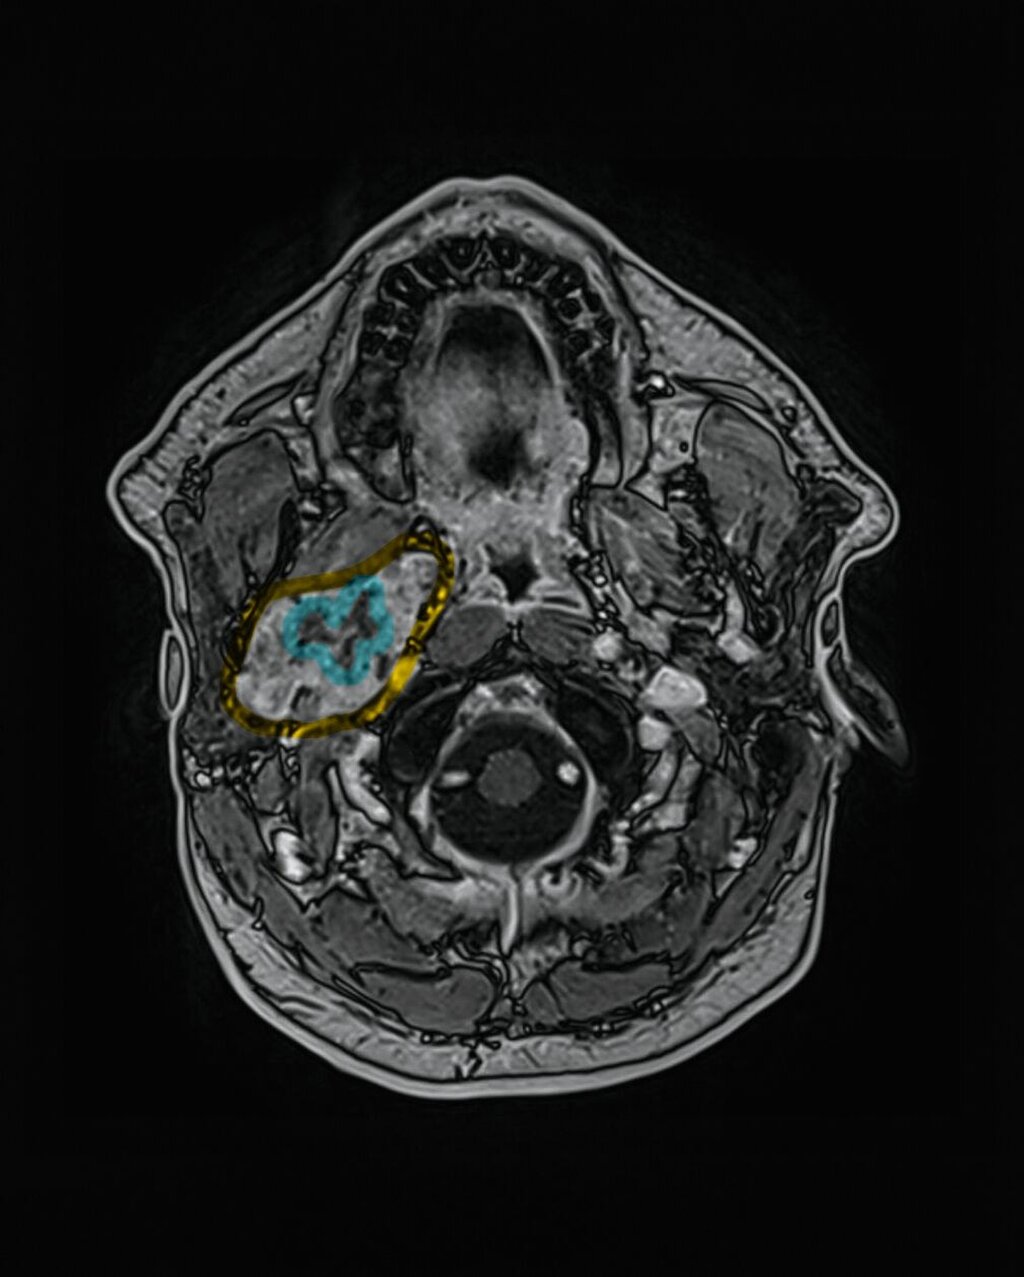

In der extern durchgeführten MRT der Halswirbelsäule vom 18. Dezember 2025 zeigte sich randständig eine angeschnittene Raumforderung im rechten Parapharyngeal- und Mastikatorraum, so dass eine gezielte weiterführende Bildgebung veranlasst wurde. Die kontrastmittelgestützte MRT vom 30. Dezember 2025 ergab eine inhomogene, gut abgrenzbare Raumforderung im rechten Parapharyngeal- und Mastikatorraum mit einer maximalen axialen Ausdehnung von 52 mm x 28 mm.

Die Läsion offenbarte ein zum Muskel isointenses T1-Signal sowie gemischt hyper- und hypointense Anteile in T2-gewichteten Sequenzen. Nach Kontrastmittelgabe imponierte eine kräftige, inhomogene Anreicherung; zentral bestanden nekrotische Areale. Eine Diffusionsrestriktion war inhomogen ausgeprägt.

Ein vaskulärer Ursprung konnte mittels dynamischer Sequenzen ausgeschlossen werden. Die Raumforderung wuchs verdrängend bis an den Musculus pterygoideus heran und hatte einen langstreckigen Kontakt von > 90° zur A. carotis interna. Zusätzlich bestand eine schlitzförmige Kompression der V. jugularis interna sowie eine fokale Teilthrombosierung der V. facialis communis. Pathologisch vergrößerte Lymphknoten waren nicht nachweisbar.

Zur besseren räumlichen Einschätzung wurde das MRT-Datenset mittels der Open-Source-Software 3D Slicer segmentiert [Fedorov et al., 2012]. Mithilfe der Funktion „Grow from seeds“ erfolgte eine separate Segmentierung des Unterkiefers und der Raumforderung, ergänzt durch manuelle Korrekturen.

Metallartefakte durch zahnärztliche Restaurationen im rechten Unterkiefer wurden berücksichtigt. Die dreidimensionale Rekonstruktion verdeutlichte die enge Beziehung des Tumors zur A. carotis interna und unterstützte die Indikationsstellung für einen erweiterten operativen Zugang.